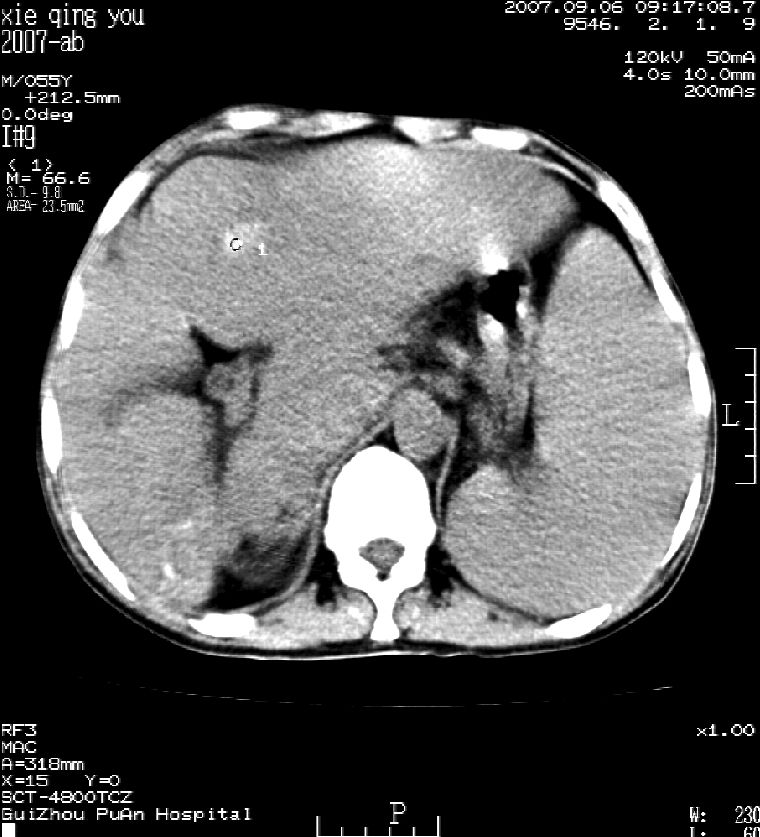

2007年9月片

因是普通ct不能做增强

这个病灶很有意思,怎么可能没有了呢?我考虑当时很可能是肝脏脓肿(b超示囊肿是有可能误诊的,因为影像表现都是低回声吗?),现在脓肿吸收了,肝脏萎缩,肝裂增宽了.别的肝叶代偿增大,不过现在左内叶的确有个占位,肝内多发结石,脾脏比以前大,不排除有肝硬化可能.建议增强扫描给于定性!!!!

肝硬化\\脾大,肝左叶肝癌可能性大,建议增强扫描.肝内胆管多发性结石.

1, 肝硬化,脾大;2,肝左叶肝癌可能性大,建议增强扫描.3,肝内胆管多发性结石.

考虑肝内胆管多发结石引起的肝内局部炎症,这样可以解释2005年肝右叶病灶的吸收和左叶新病灶.